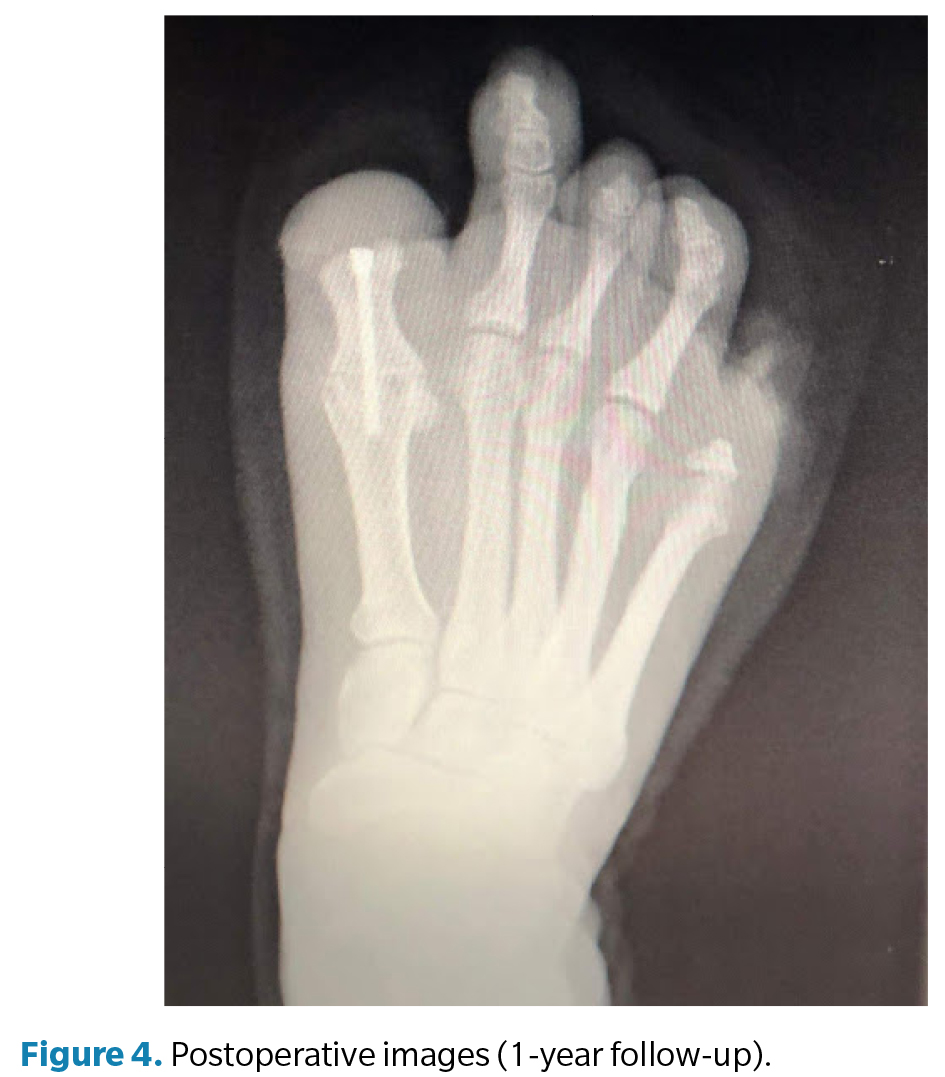

The postoperative period included periodic dry dressings and progressive functional follow-up. At 3 months, complete pain resolution and significant improvement in gait quality were observed. At 6 months, the patient showed satisfactory functional recovery, allowing temporary medical discharge. Customized silicone digital prostheses were later fabricated for both feet to improve podiatric symmetry, load distribution, and psychosocial acceptance. At 12-month follow-up, the patient remained asymptomatic, with complete radiographic consolidation of the arthrodesis, correct alignment of the first ray, and stable gait without limitations, confirming the functional success of the procedure.